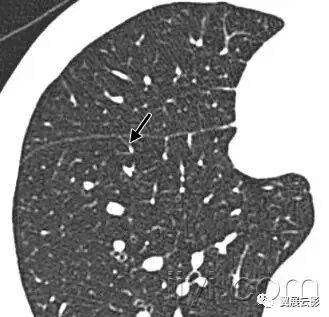

十八、小叶中心性:

解剖:小叶中心性用于描述次级肺小叶的支气管血管束中心区域。病理学上也用这一术语描述终末小支气管远端,位于呼吸性细支气管和肺泡管中心的病变。

CT:正常次级肺小叶中心的点状或者线状的密度增高影,胸膜下25px范围内最明显,代表小叶内的动脉,直径约1mm。

小叶中心性异常包括(1)结节(2)树芽征,提示小气道病变(3)由于临近间质的增厚或者浸润导致小叶中心结果更加清晰(4)小叶中心性肺气肿导致的异常低密度。

附图为小叶中心性肺气肿